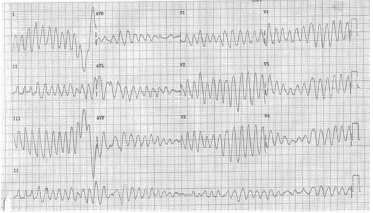

Identifique o medicamento que está mais associado à arritmia abaixo.

Provas